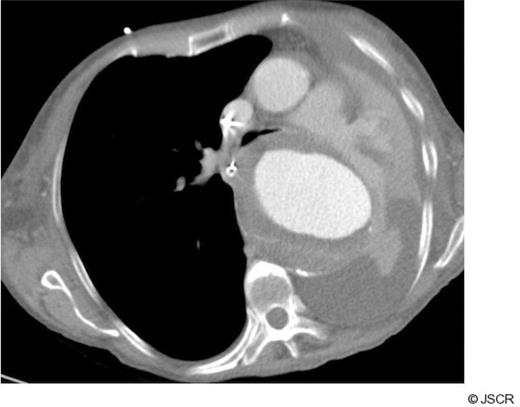

CT scanning revealed a large descending thoracic aortic aneurysm measuring 8 cm in maximum diameter (Fig 2). The left main bronchus was compressed between the aneurysm and the aortic trunk (Fig 3). The patient was regarded as unfit for an open replacement of the aneurysm. The neck of the aneurysm was markedly conical immediately distal to the left subclavian artery, so proximal stent graft placement would have necessitated left common carotid artery and left subclavian artery bypass grafting to provide a parallel proximal landing zone. The distal neck was also markedly conical with a diameter of 42 mm at the coeliac axis, with extensive mural thrombus. These features rendered a successful endovascular repair unlikely, and therefore endovascular interventional was discounted.

CT chest showing complete compression of left main bronchus by large aortic aneurysm